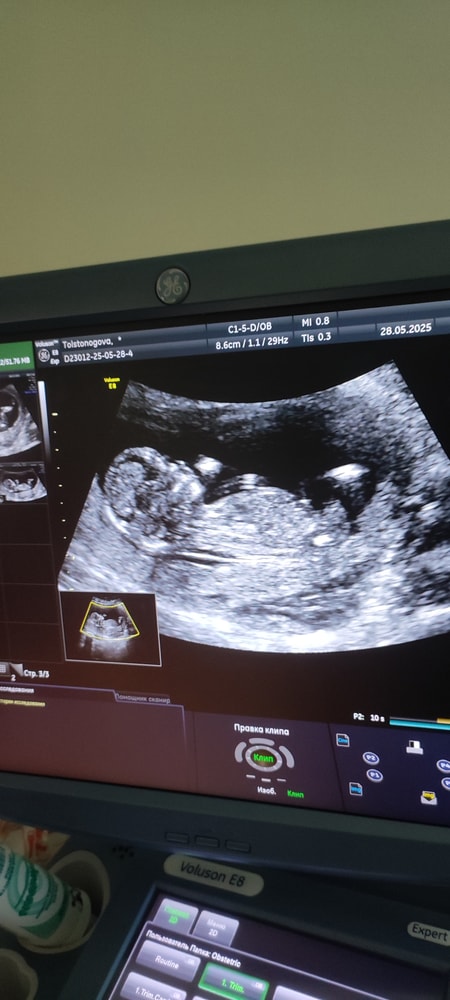

Девочки, посмотрите) девочка или мальчик?)

Не видно полового бугорка ☺️

А мне кажется девочка)

По моему мальчик )

Кажется девочка)

Сынок🙂

Мальчик)

Вроде мальчик

Наталья, у вас вроде меньше 30 градусов

Ол, я вот думаю, половой бугорок это или нет. Если это он, то склоняюсь к девочке.